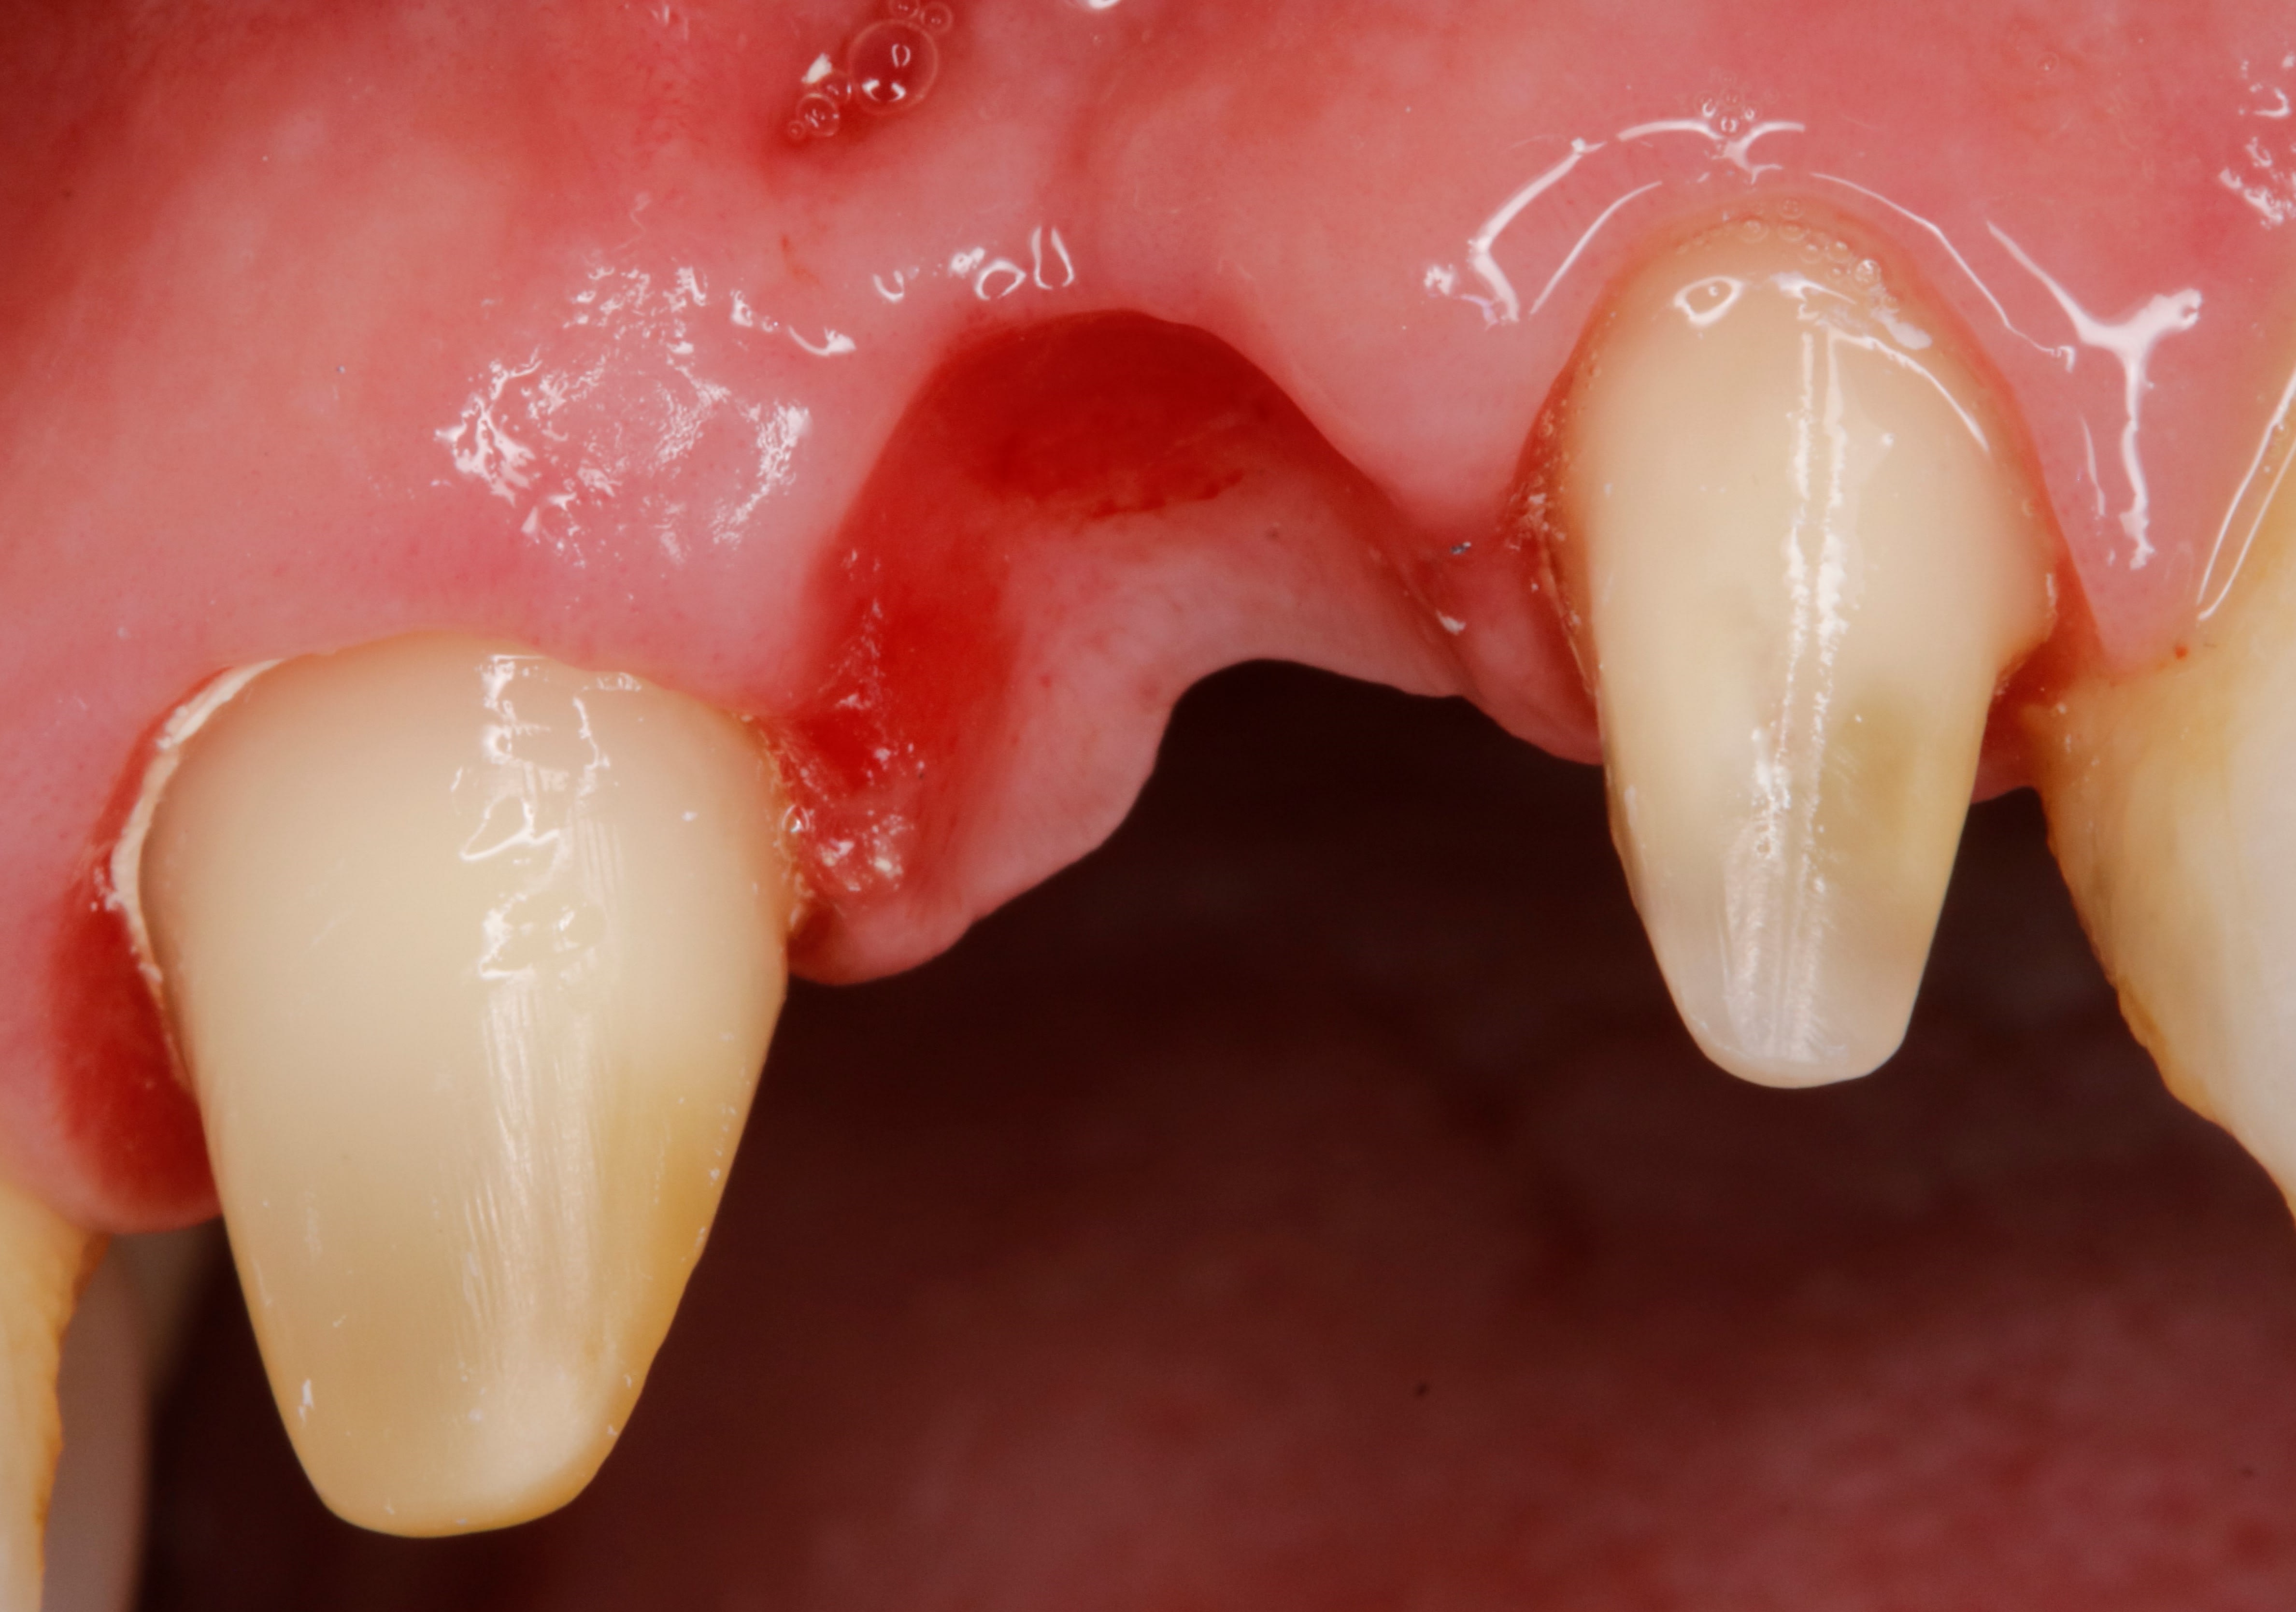

j'ai fait 2 couronnes en zircon solidarisées sur 24+25 + inter 23

autrement dit un bridge avec extension .

Waouh, du zircone pour un bridge avec extension, c'est couillu !

un peu oui , mais ça ça vient vite quand tu ne poses pas d implant :-)

je pense que les dents partiront avant que l extension ne se casse .

J’ai le davier qui me démange…

Il est garanti combien de temps ton bridge ?

on ne garanti pas le HN :-)

je le considère comme un prov de luxe qui devrait tenir au moins 5 ans voir plus , elle a 77 ans et s il faut elle partira avec .

c est une béance avec 24 et 25 très mobile , enfin elles l étaient avant le prov .

c est un pb ce zircon full , en fait c est une grosse merde . surtout ces zircons jolis c est fragile pour les bridges .

d un autre coté , sur un cas comme ça , si tu fais de la ccm alors là c est sur que tu as un pb paro tout de suite avec perte des dents rapidement .

du coup , quoi faire d autre ? devant c est un bridge que j ai fait en 2018 et c était bien pire , en attendant les implants qu elle n a jamais fait .